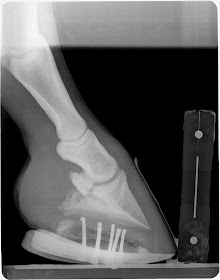

This is a case with navicular bone changes that had responded to increase in palmar angle and reduction in digital breakover but was not consistently going sound. Dr. Redden applied an aluminum rocker rail. Look at the TSA and the distance the navicular is from the proximal p2 between the pre and post shoe radiographs.

This is a many year chronic laminitis. Goal with the rockered aluminum rail is to decrease DDFT tension unloading the apex of the coffin bone and the tension forces at the horn/lamellar zone. This places breakover in the center of articulation. This will improved compromised circulation in the dorsal region of hoof and a more even hoof growth from toe to heel is expected as well as improved sole depth.